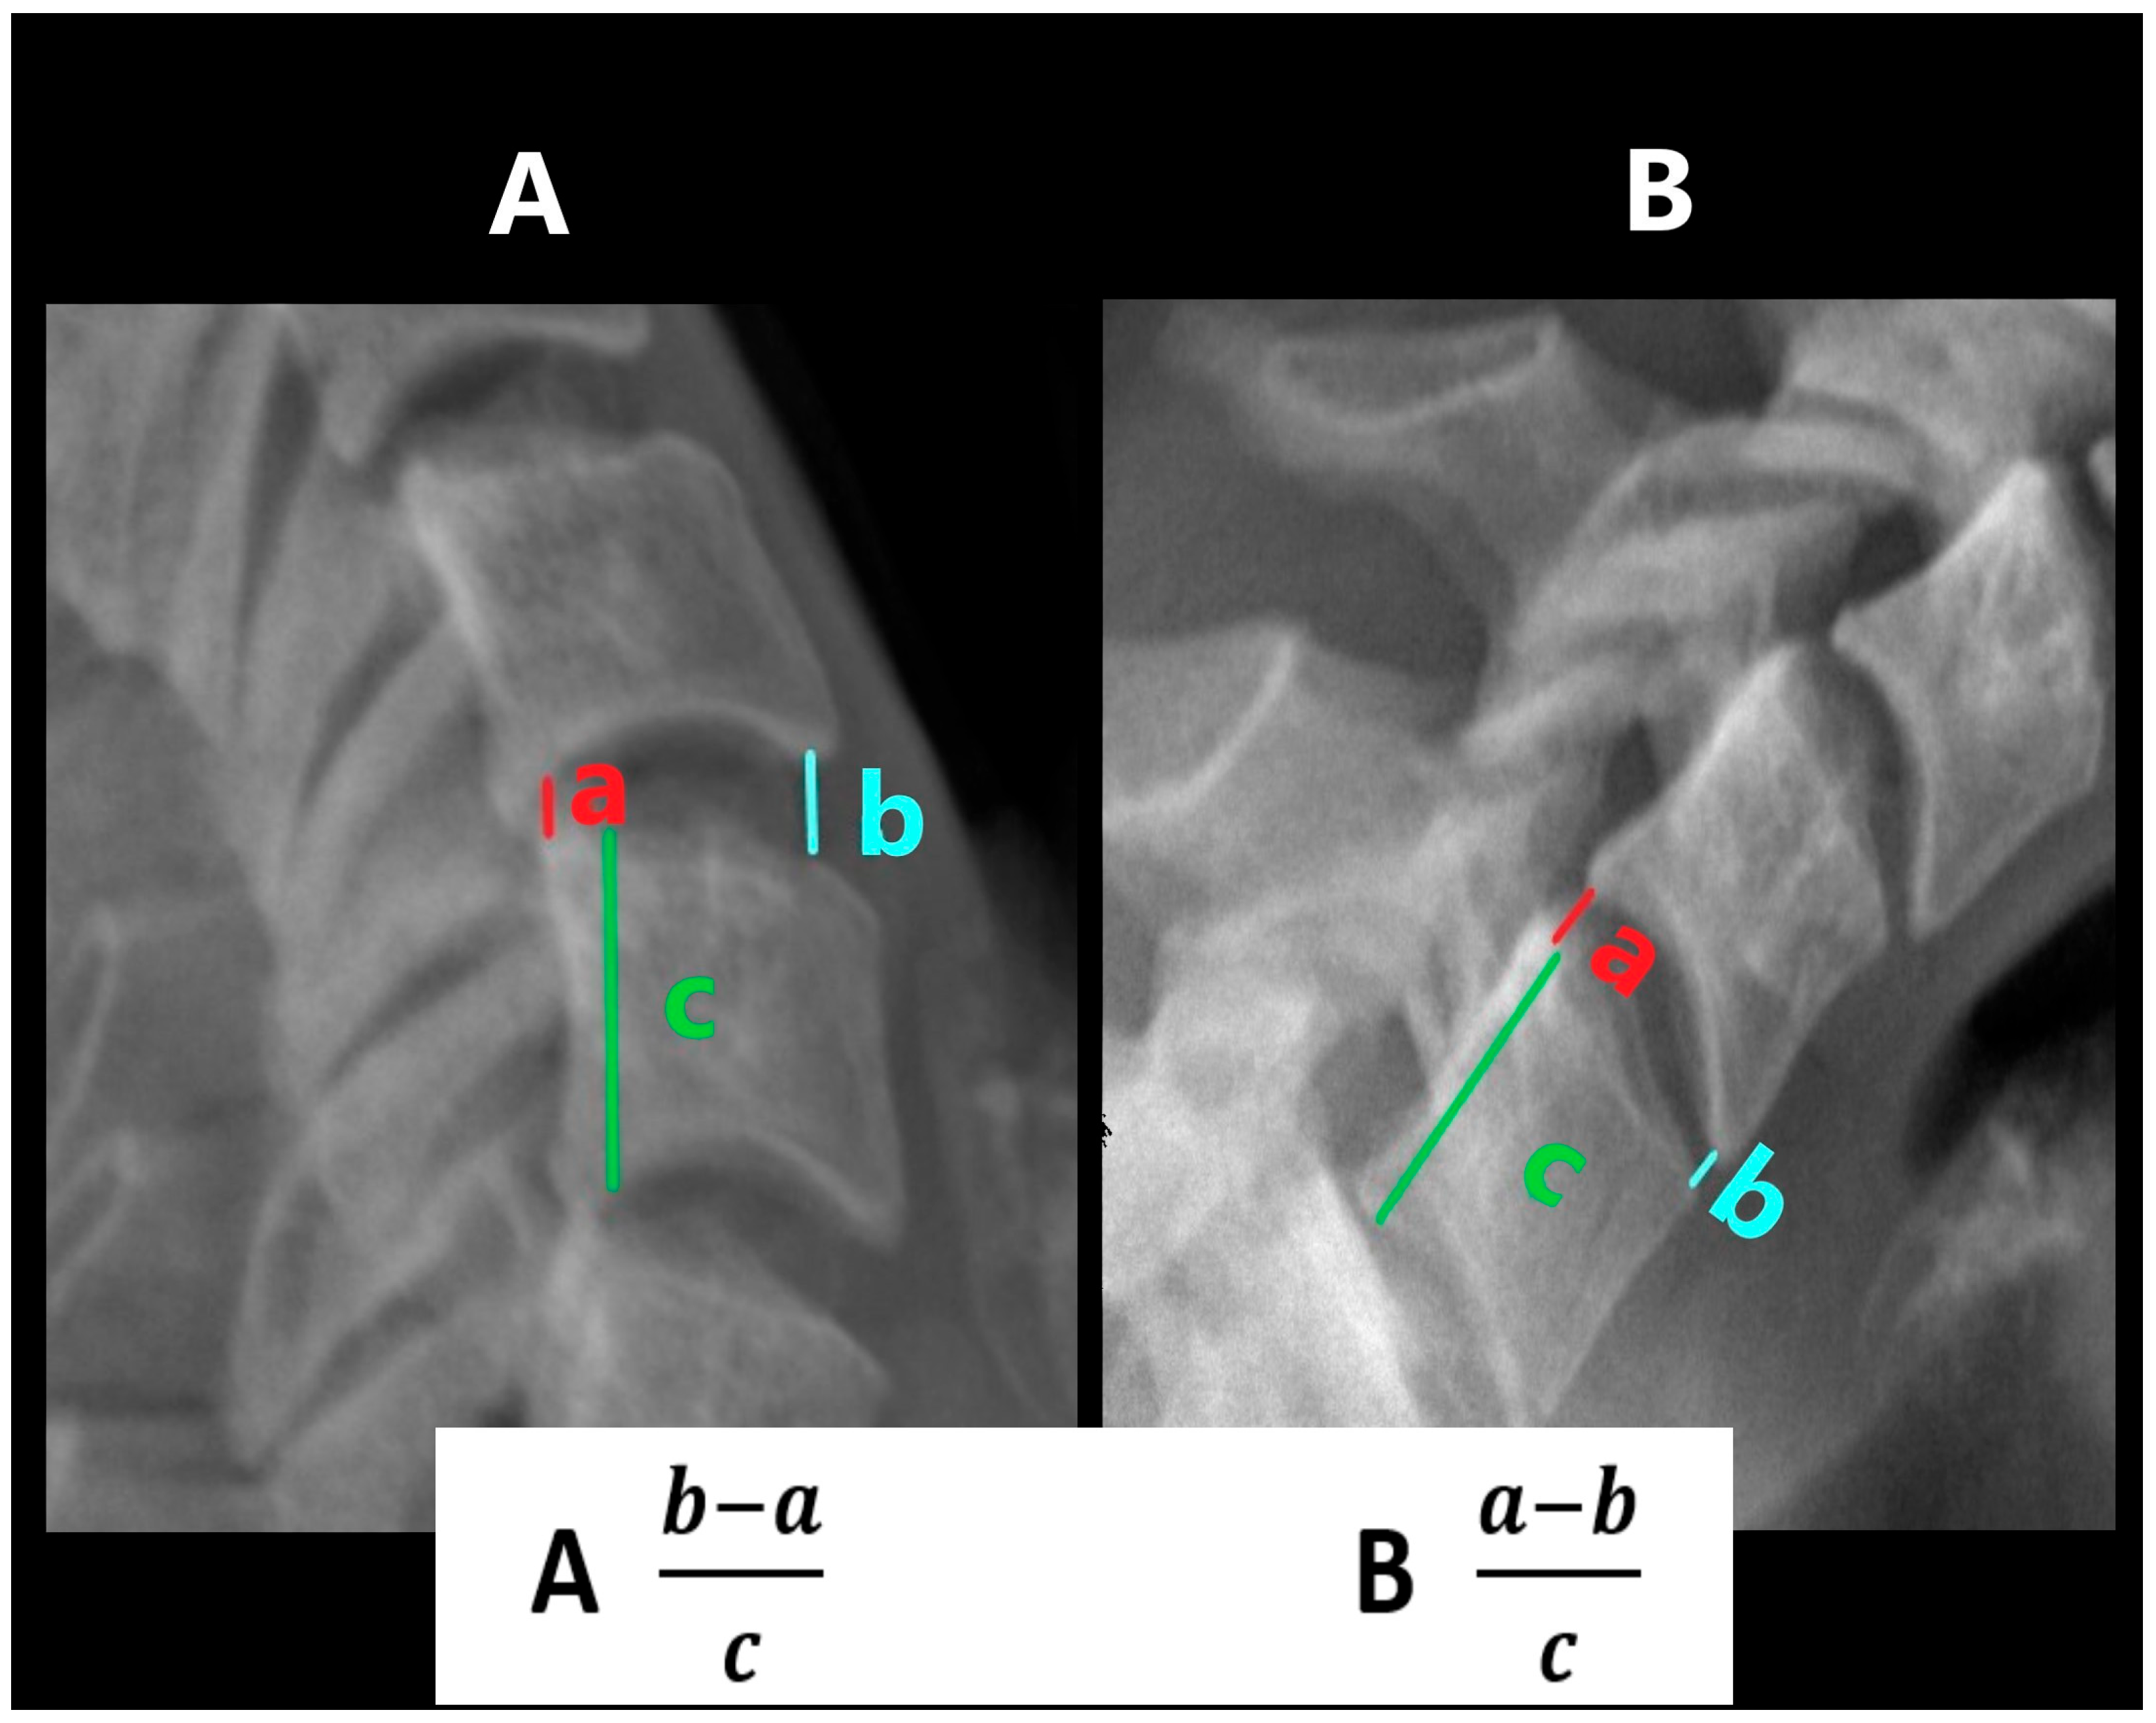

The Cobb angle was determined as the angle between two straight lines drawn tangentially to the lower edge of the C2 and C7 (Figure 1) [9,10]. Where the lower edge of C7 was not visible in the examination, due to the patient’s inability to take the required position, a C2–C6 substitute measurement with comparable diagnostic value was made [11]. Where the lower edge of the C6 vertebra was also unavailable, the measurements were abandoned (a total of 13 examinations in 11 patients). After taking measurements in functional projections, the sum of the obtained values was also calculated.

Figure 1. Cobb’s angle measurement: (A)—in flexion, (B)—in extension.